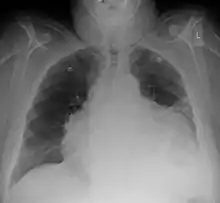

Chest x-ray: is non-specific and may not help identify a pericardial effusion but a very large, chronic effusion can present as "water-bottle sign" on an x-ray, which occurs when the cardiopericardial silhouette is enlarged and assumes the shape of a flask or water bottle.[2] Chest radiograph is also helpful in ruling out pneumothorax, pneumonia, and esophageal rupture.

Pericardial effusion due to malignancy. Note bulbous heart and primary lung cancer in right upper lobe.